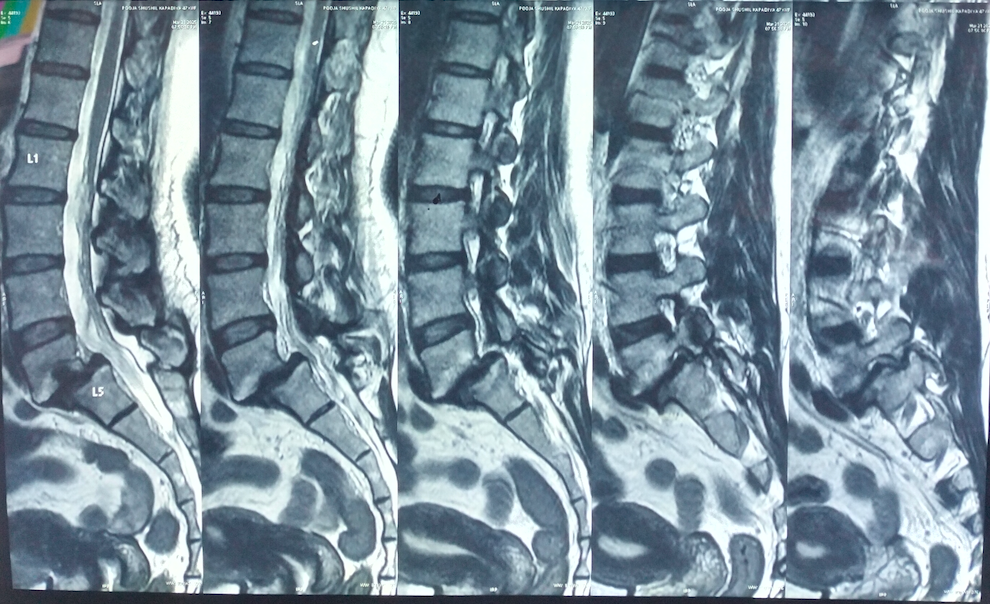

- MRI – Best for early stress reactions and soft tissue assessment

Spondylolysis is a condition characterized by a stress fracture or defect in the pars interarticularis, a small but critical portion of a vertebra. It most commonly affects the lower lumbar spine, especially the L5 vertebra, and is a frequent cause of back pain in adolescents, athletes, and young adults.

Many patients may initially be asymptomatic and are diagnosed incidentally.